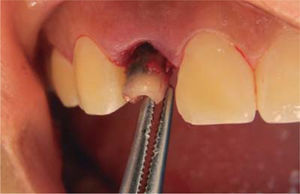

Anestesia local infiltrativa (lidocaína clorhidrato al 2% roxicaína) fue aplicada en la zona del incisivo lateral superior derecho, después de esto la exodoncia preservando el alvéolo (Figura 3). Se coloca un implante Replace Select (Nobel Biocare) de 3.5 x 13 mm. La estabilidad primaria del implante fue confirmada mediante la inserción de torque a 35 Ncm; para compensar las alteraciones de la pared vestibular, el espacio entre el implante y la pared bucal fue sellada con injerto óseo Bi-Oss de partícula pequeña medular (Geistlich Pharma) (Figura 4). A continuación fue provisionalizado de manera inmediata con un pilar plástico prefabricado (Nobel Biocare) (Figura 5).